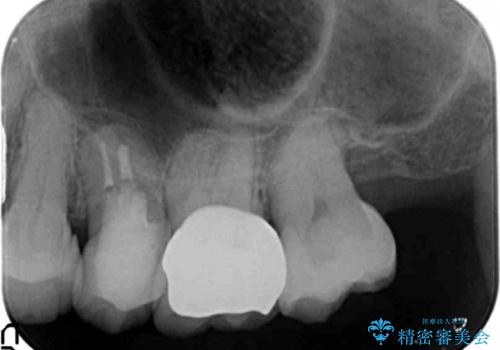

- 左上5番の根の治療途中で転院希望で来院。

割れているために抜かないといけないと説明されたとのことでした。

特に割れている所見はなかったため、根の治療から被せ物まで治療を行いました。

奥の銀歯のやりかえも希望されたため、セラミッククラウン、インレーにする治療をしています。

- 合計 48.4万円( 左上5:再根管治療 9万円、ファイバーコア2万円、仮歯1万円、ジルコニアクラウン10万円 左上6:仮歯、ジルコニアクラウン 左上7:emaxインレー7万円)費用は治療当時の料金となります

左上6番のアンレーは、歯の破折を防ぐためにクラウンとしました。